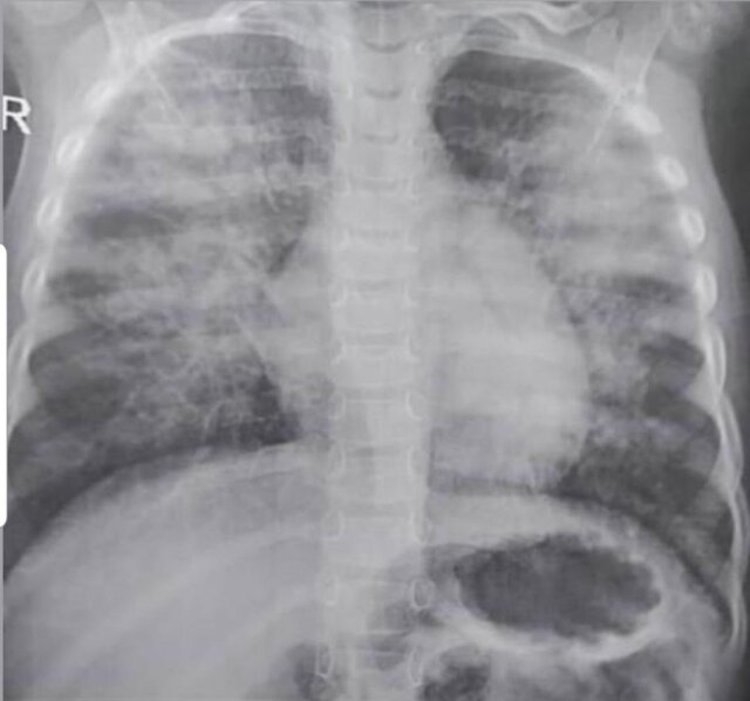

رویداد۲۴ دکتر عرفان مردانی با انتشار عکس رادیولوژی یک کودک خوزستانی فوتشده بر اثر کرونای انگلیسی، در صفحه شخصی خود در توییتر نوشت: "عکس ریه کودک ۳ ساله خوزستانی که به علت تهاجم سنگین کرونای انگلیسی در کمتر از سه ساعت از ورودش به بیمارستان جان باخت.

گناه این طفل معصوم چه بود که باید قربانی سهلانگاریها شود.

مراقب باشید و احساس خطر کنید، کرونا دیگر پیر و جوان نمیشناسد. "